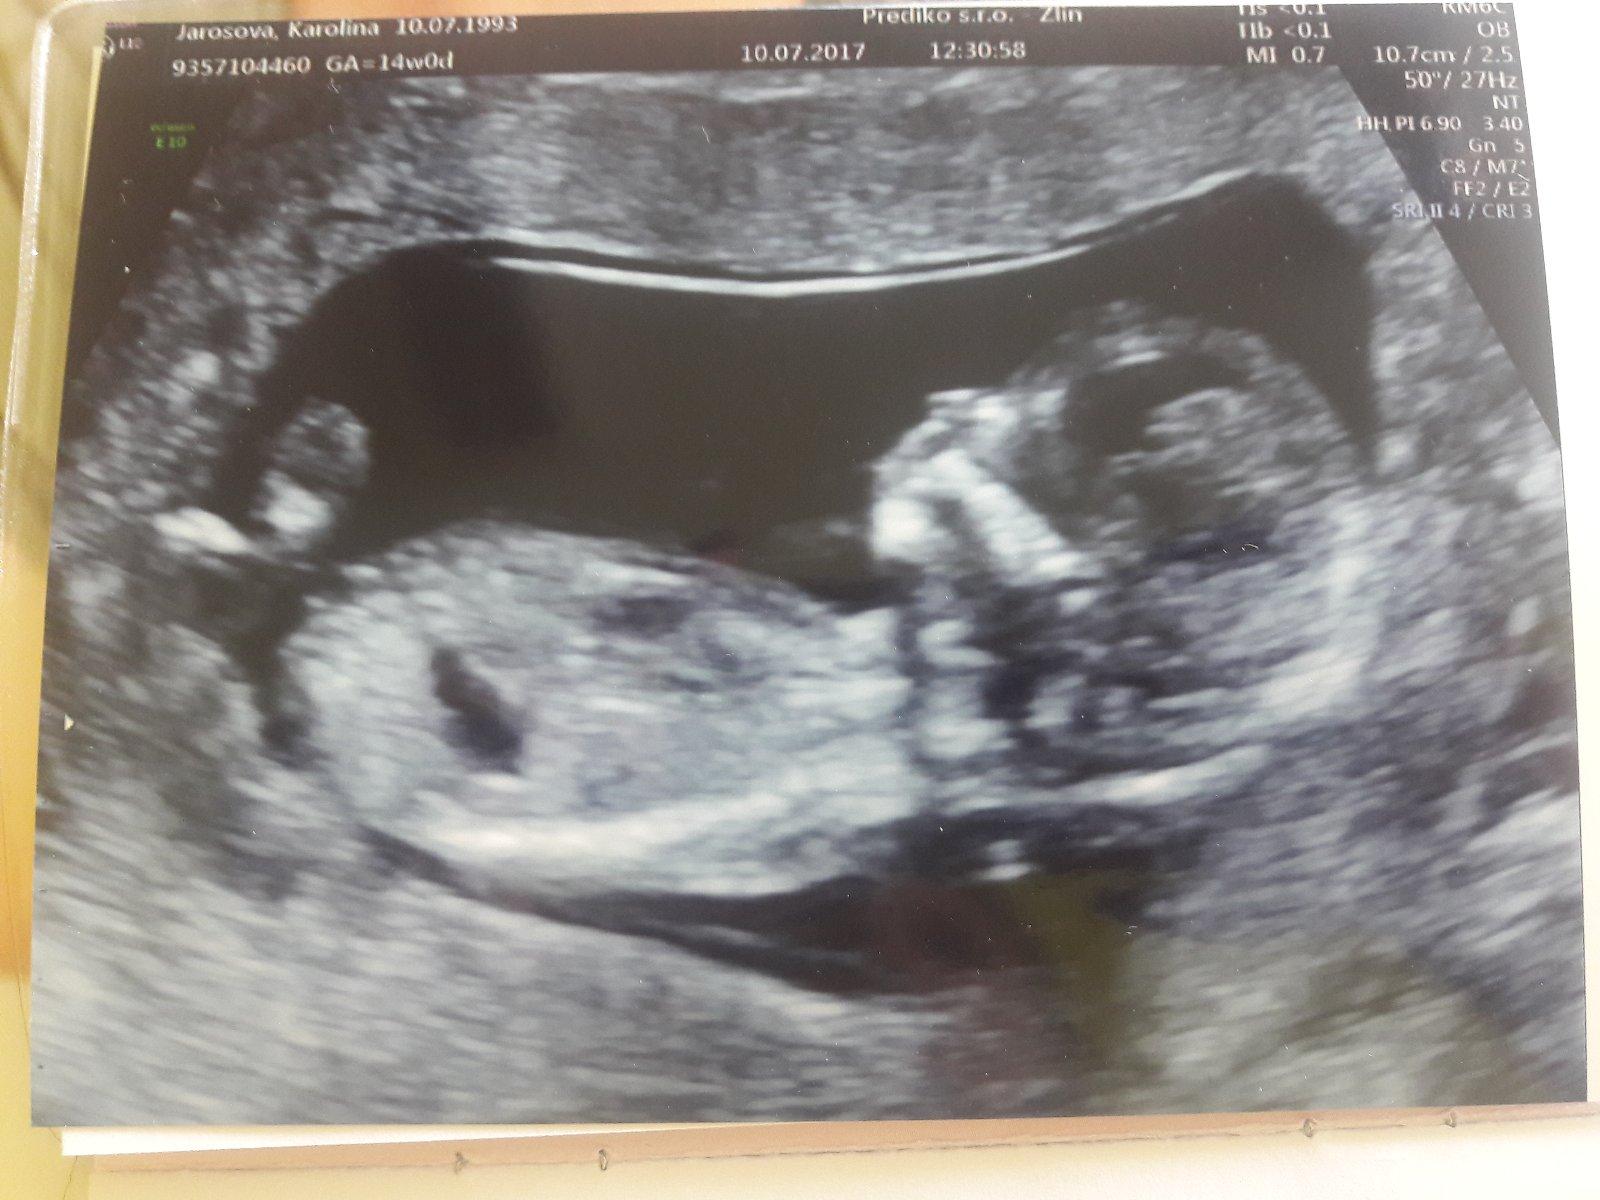

@barushe_27 holky, co myslite, ze kdo vykouka na fotkach z profilu? Pokud diteti neni videt mezi nohy nebo nekdo nema rentgenove oci, tak se to proste rict neda. Ale v obou pripadech bych si tipla, ze na 50% to bude chlapecek!

@barushe_27 už más potvrzeno, jestli holčička nebo chlapeček? 🙂

@mariejosef dekuji za vas nazor nevadi ze cekam chlapecka aspon me ochrani 😁 mam doma 2 a moc je miluju a tohodle budu taky jinak dekuji 🙂